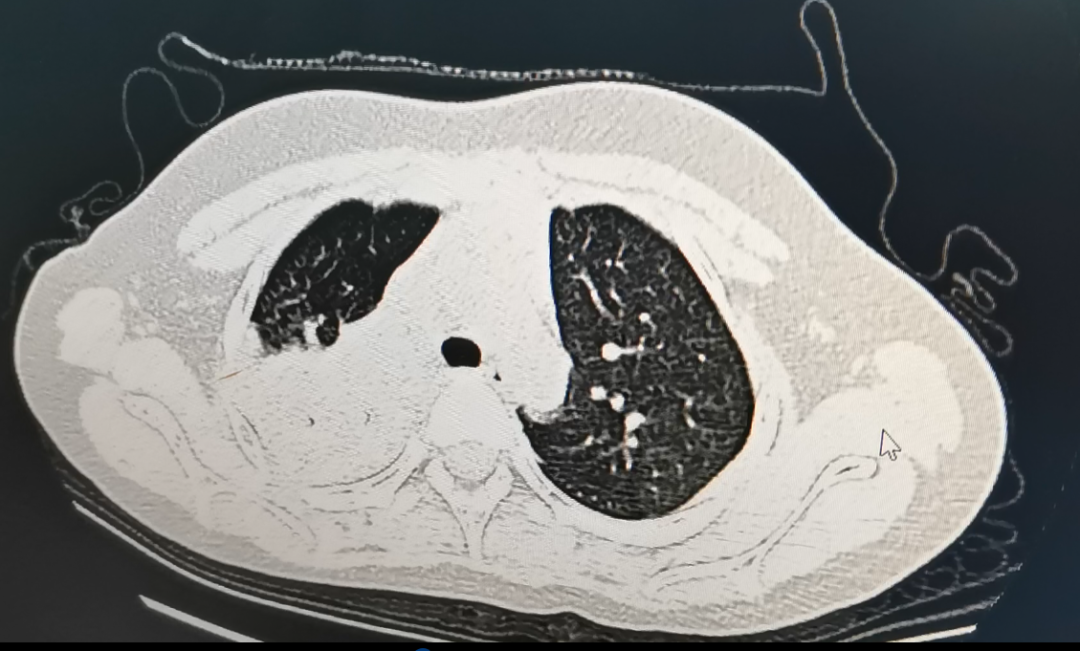

经由CT搜检发现

她传染了肺炎支原体

肺部酿成了“白”肺

传染早期肺部查体或者无显着非常。若是病情进展敏捷、有多肺叶浸润、治疗后72小时持续高热不退、呼吸难题示意,需要小心有成长为重症的风险,建议实时完美胸部影像学搜检评估肺部情形。